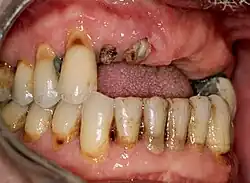

Wurzelreste der Zähne 11, 12